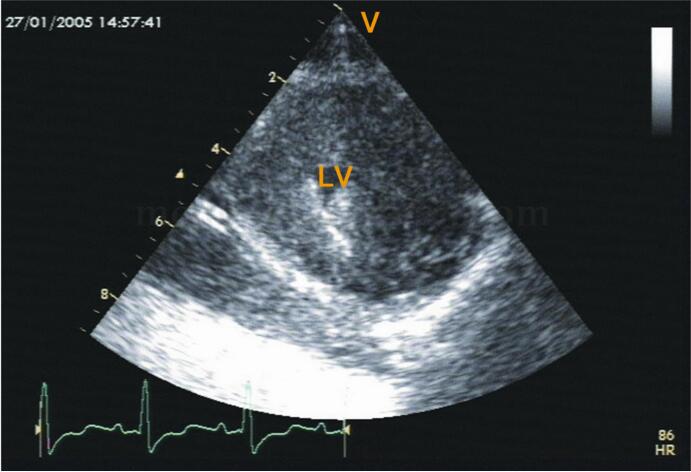

图2‐1‐201 左室短轴心尖水平切面心尖部心肌明显增厚致心腔近乎闭塞

5)均匀肥厚型心肌病:各切面均可见各室壁明显均匀一致的增厚,回声增强,心腔明显变小(图2‐1‐202,图2‐1‐203),一般无左室流出道狭窄。